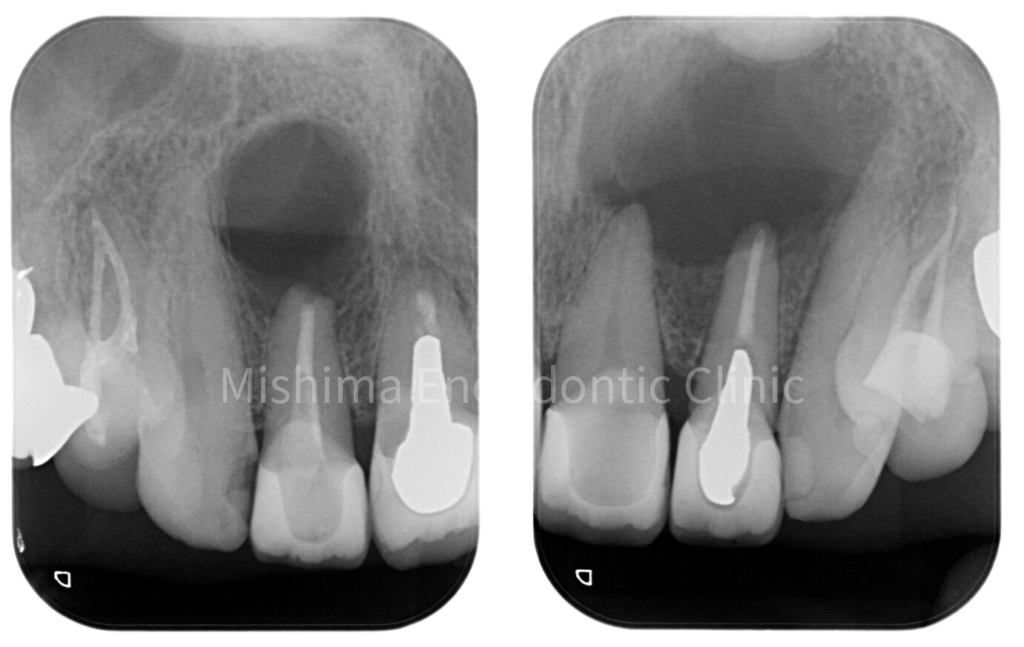

After

術後 1年